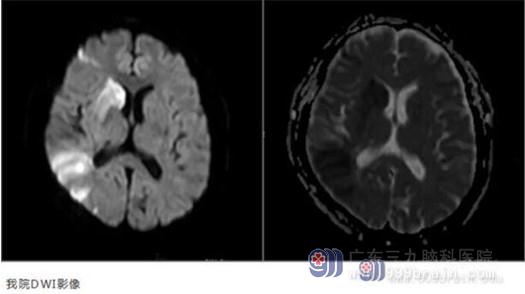

到达医院后,主管医生潘梦秋主治医生立即完善相关检查。查体:双眼向右侧凝视,左侧鼻唇沟变浅,伸舌左偏,构音不清,四肢肌张力正常,左上肢肌力4级,左下肢肌力3-级。我院DWI提示右侧颞叶、基底节-放射冠区急性脑梗塞;MRA提示右侧大脑中动脉闭塞。

经综合评估,患者具有静脉溶栓指征,无相关禁忌症。在告知患者家属病情及溶栓风险,并取得知情同意后,决定予以rt-PA静脉溶栓治疗。溶栓后1小时,患者症状得到改善,NIHSS评分由7分降为4分,但复查MRA,检查结果提示右侧大脑中动脉部分显影,考虑患者右侧大脑中动脉仍存在狭窄。